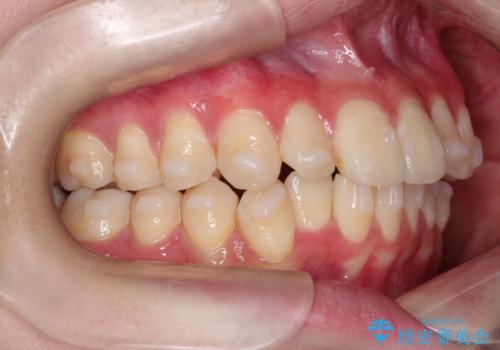

- 上下の前歯に捻れ(捻転)とガタつき(叢生)が見られます。

上の2番目の前歯の捻れに関しては、元々歯の大きさが小さい歯であるため、マウスピースにて力がかかりにくく、捻転の改善が一般的に難しくなりがちです。

下の犬歯に関しても捻れと傾き、ガタつきが大きく、歯根の長さも相まって移動の難易度が高くなりがちです。

インビザラインのそうした特色を踏まえた上で、それらをリカバーできるように治療方式の調整を十分に行い、治療を進めました。